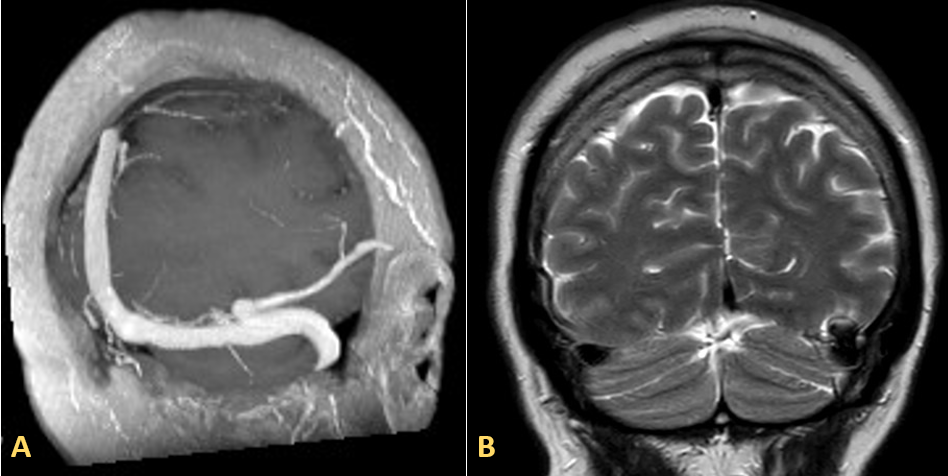

Magnetic resonance image (MRI) of the brain with contrast showed focal ectasia of the vein of Labbé in its retrograde trajectory to the Sylvian fissure with varicose dilatation at the confluence with the left transverse sinus and edema in the adjacent temporal gyri. No signs of acute thrombosis were present (Figure 1).